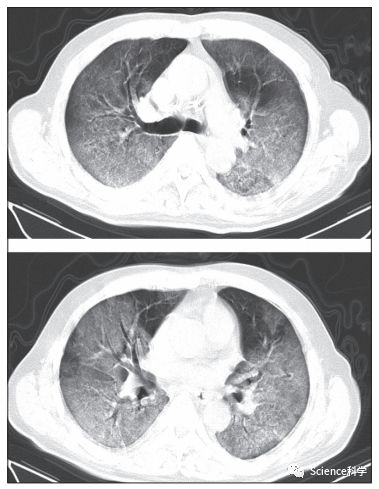

实际上,研究团队也着重关注了有既往病史的患者。下图是一名患有慢性肺病(结核病)、入院第 12 天因呼吸窘迫症去世的 60 岁男性患者的不同级别的 CT 影像。根据其发病第 8 天的 CT 影像,两肺可见广泛的磨玻璃影,几乎累及整个下叶、大部分上叶和右肺中叶,“白肺”(肺部显影呈一大片的白色状,一般是肺部被炎症所侵润的表现),并伴有空气支气管造影。